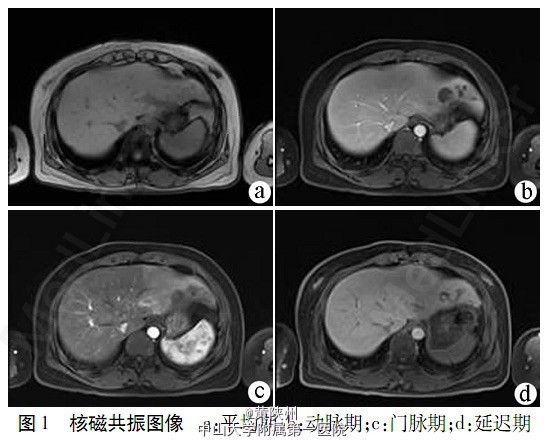

查体:无肝掌、蜘蛛痣,皮肤巩膜无黄染,心肺听诊无异常,腹平软,无压痛及反跳痛,肝脾肋下未及,肝区叩痛阳性,墨菲征阳性,移动性浊音阴性,双下肢不肿。 白细胞4.64×109/L,血红蛋白129g/L,血小板233×109/L,嗜酸性粒细胞绝对值1.14×109/L,嗜酸粒细胞24.6%;肝功能:ALT 13.7U/L,AST 12.9U/L,TBil 15.9 μmol/L,Alb43.8 g/L,GGT40.1U/L,ALP81.9U/L,CHE4600U/L;肿瘤标志物:甲胎蛋白、癌胚抗原、糖链抗原-19-9、糖链抗原72-4均在正常范围,HBV、HCV、HEV现症感染指标阴性,自身抗体系列无异常。本院MRI示:肝左叶外侧段多发大小不等不规则病灶,增强扫描肝左叶外侧段多发病灶动脉期强化不显著,平衡期可见边缘强化及内部分隔样强化,动脉期肝左叶外侧段见楔形强化,较大病灶远端胆管扩张。肝左叶外侧段多发占位,并肝左叶灌注异常(图1)。

根据患者肿瘤家族史、腹部影像学检查诊断考虑胆管细胞癌可能性大,但患者伴发热、腹痛,因此不除外肝脓肿;曾在广西疫区居住,嗜酸粒细胞明显升高,肝寄生虫病不除外。经外科会诊后考虑有外科手术指征。于2013年2月28日行剖腹探查手术:肝脏左外叶可见多发占位性病变,最大约4cm×3cm×2cm,胆囊大小9cm×4cm×1.5cm,胆囊壁充血水肿,囊内未及结石及占位性病变,胆总管明显扩张约1.1cm。术中对占位病变取病理,冰冻病理结果回报嗜酸性肉芽肿可能。术中诊断:肝左叶嗜酸性肉芽肿,寄生虫感染?胆囊呈急性胆囊炎性改变,决定行肝左外叶切除+胆囊切除+胆总管探查+T管引流术。胆道镜于胆总管开口处进入,于胆总管下端发现有1寄生虫,以取石钳取出,见虫体呈片状,肉红色,大小约2cm×1cm×0.3cm(图2),蠕动活跃。 于胆道切开处放置T管一根。后经鉴定,肝片形吸虫。术后每日引流胆汁400ml左右,未再引流出寄生虫。术后第2日化验血常规中嗜酸性粒细胞绝对值降至0.06×109/L,嗜酸性粒细胞百分比0.5%。术后第6胆汁引流<10 ml,术后2周出院,出院后赴友谊医院就诊,服用吡喹酮片0.6g/次,2次/d(服2d),术后2个月复查胆道镜未见虫体及异常遂拔除引流管。